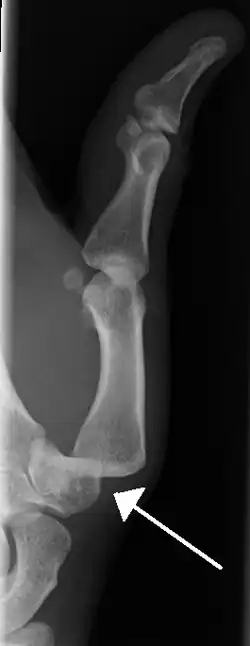

-

Radiograph of right fifth phalanx dislocation resulting from bicycle accident -

Right fifth phalanx dislocation resulting from bicycle accident